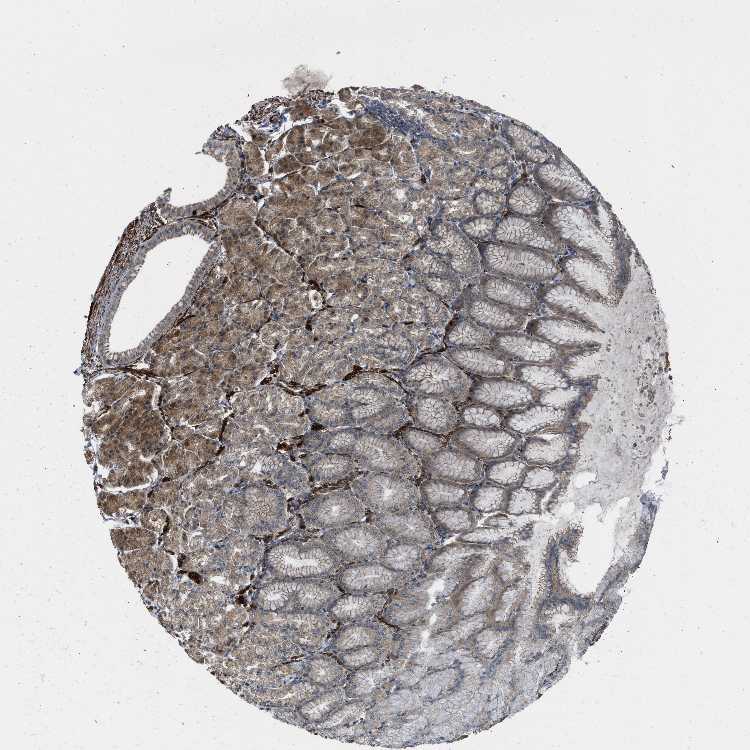

STOMACH 1 - Antibody stainingi

Antibody staining in the annotated cell types in the current human tissue is reported as not detected, low, medium, or high, based on conventional immunohistochemistry profiling in selected tissues. This score is based on the combination of the staining intensity and fraction of stained cells.

Each image is clickable and will lead to virtual microscopy that enables deeper exploration of all samples and also displays staining intensity scores, fraction scores and subcellular localization as well as patient and tissue information for each sample.

Antibody HPA018191

Glandular cells High